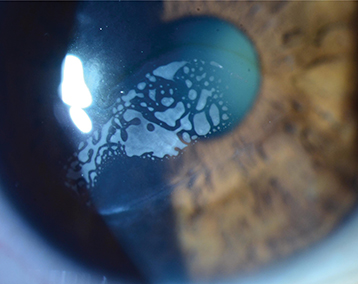

Epithelial ingrowth into flap interface (see Figure 4.31.2).